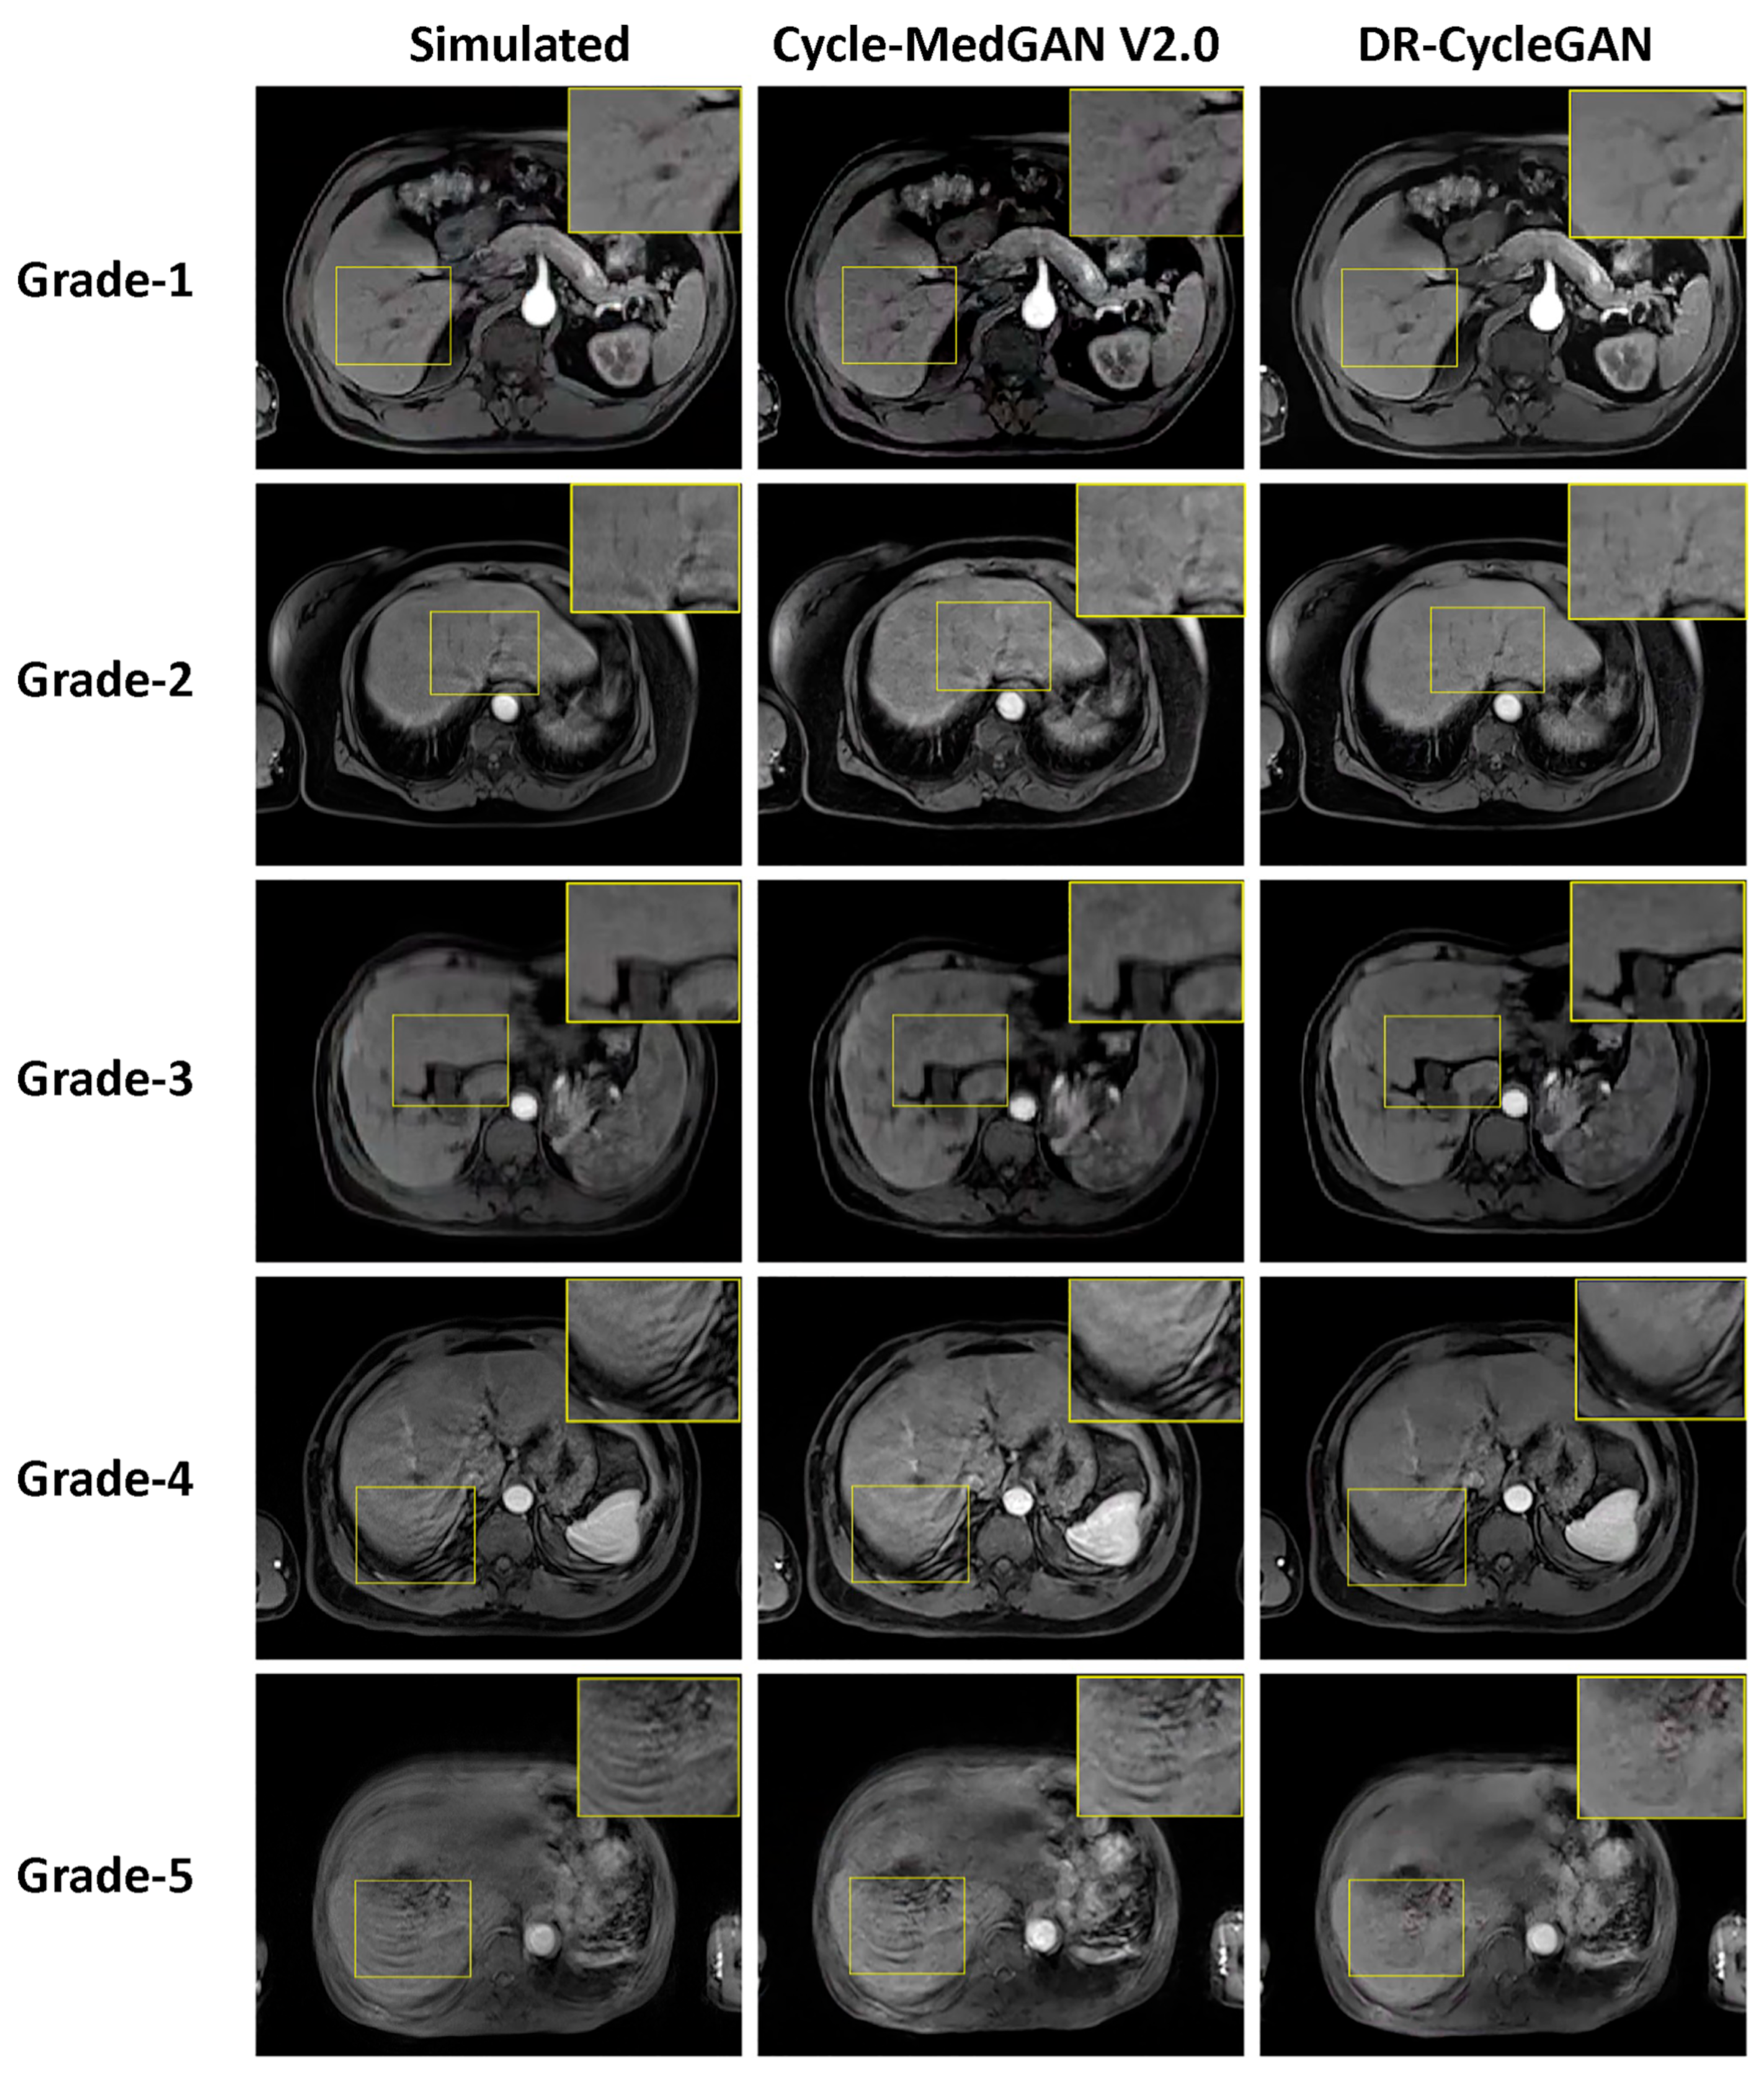

3.1. Evaluation of Paired Simulated Test Dataset

| Motion artifact grades | |

| DR-CycleGAN | 2.7 ± 0.7 * |

| Cycle-MedGAN V2.0 | 3.0 ± 0.9 * |

| Simulated corrupted image data | 4.0 ± 0.8 * |